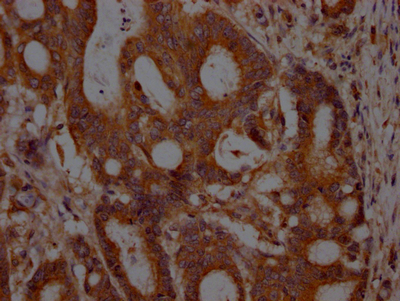

IHC image of CSB-RA634199A0HU diluted at 1:100 and staining in paraffin-embedded human colon cancer performed on a Leica BondTM system. After dewaxing and hydration, antigen retrieval was mediated by high pressure in a citrate buffer (pH 6.0). Section was blocked with 10% normal goat serum 30min at RT. Then primary antibody (1% BSA) was incubated at 4℃ overnight. The primary is detected by a Goat anti-rabbit IgG polymer labeled by HRP and visualized using 0.05% DAB.